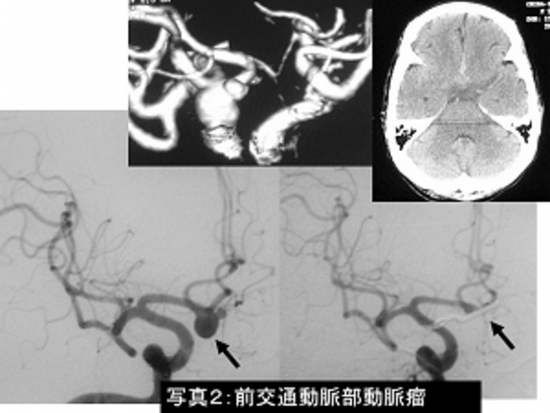

写真2:くも膜下出血(前交通動脈瘤)に対するクリッピング術です。

左は手術前の脳血管撮影、右は手術後の脳血管撮影で動脈瘤(→)がクリップにより消失しています。